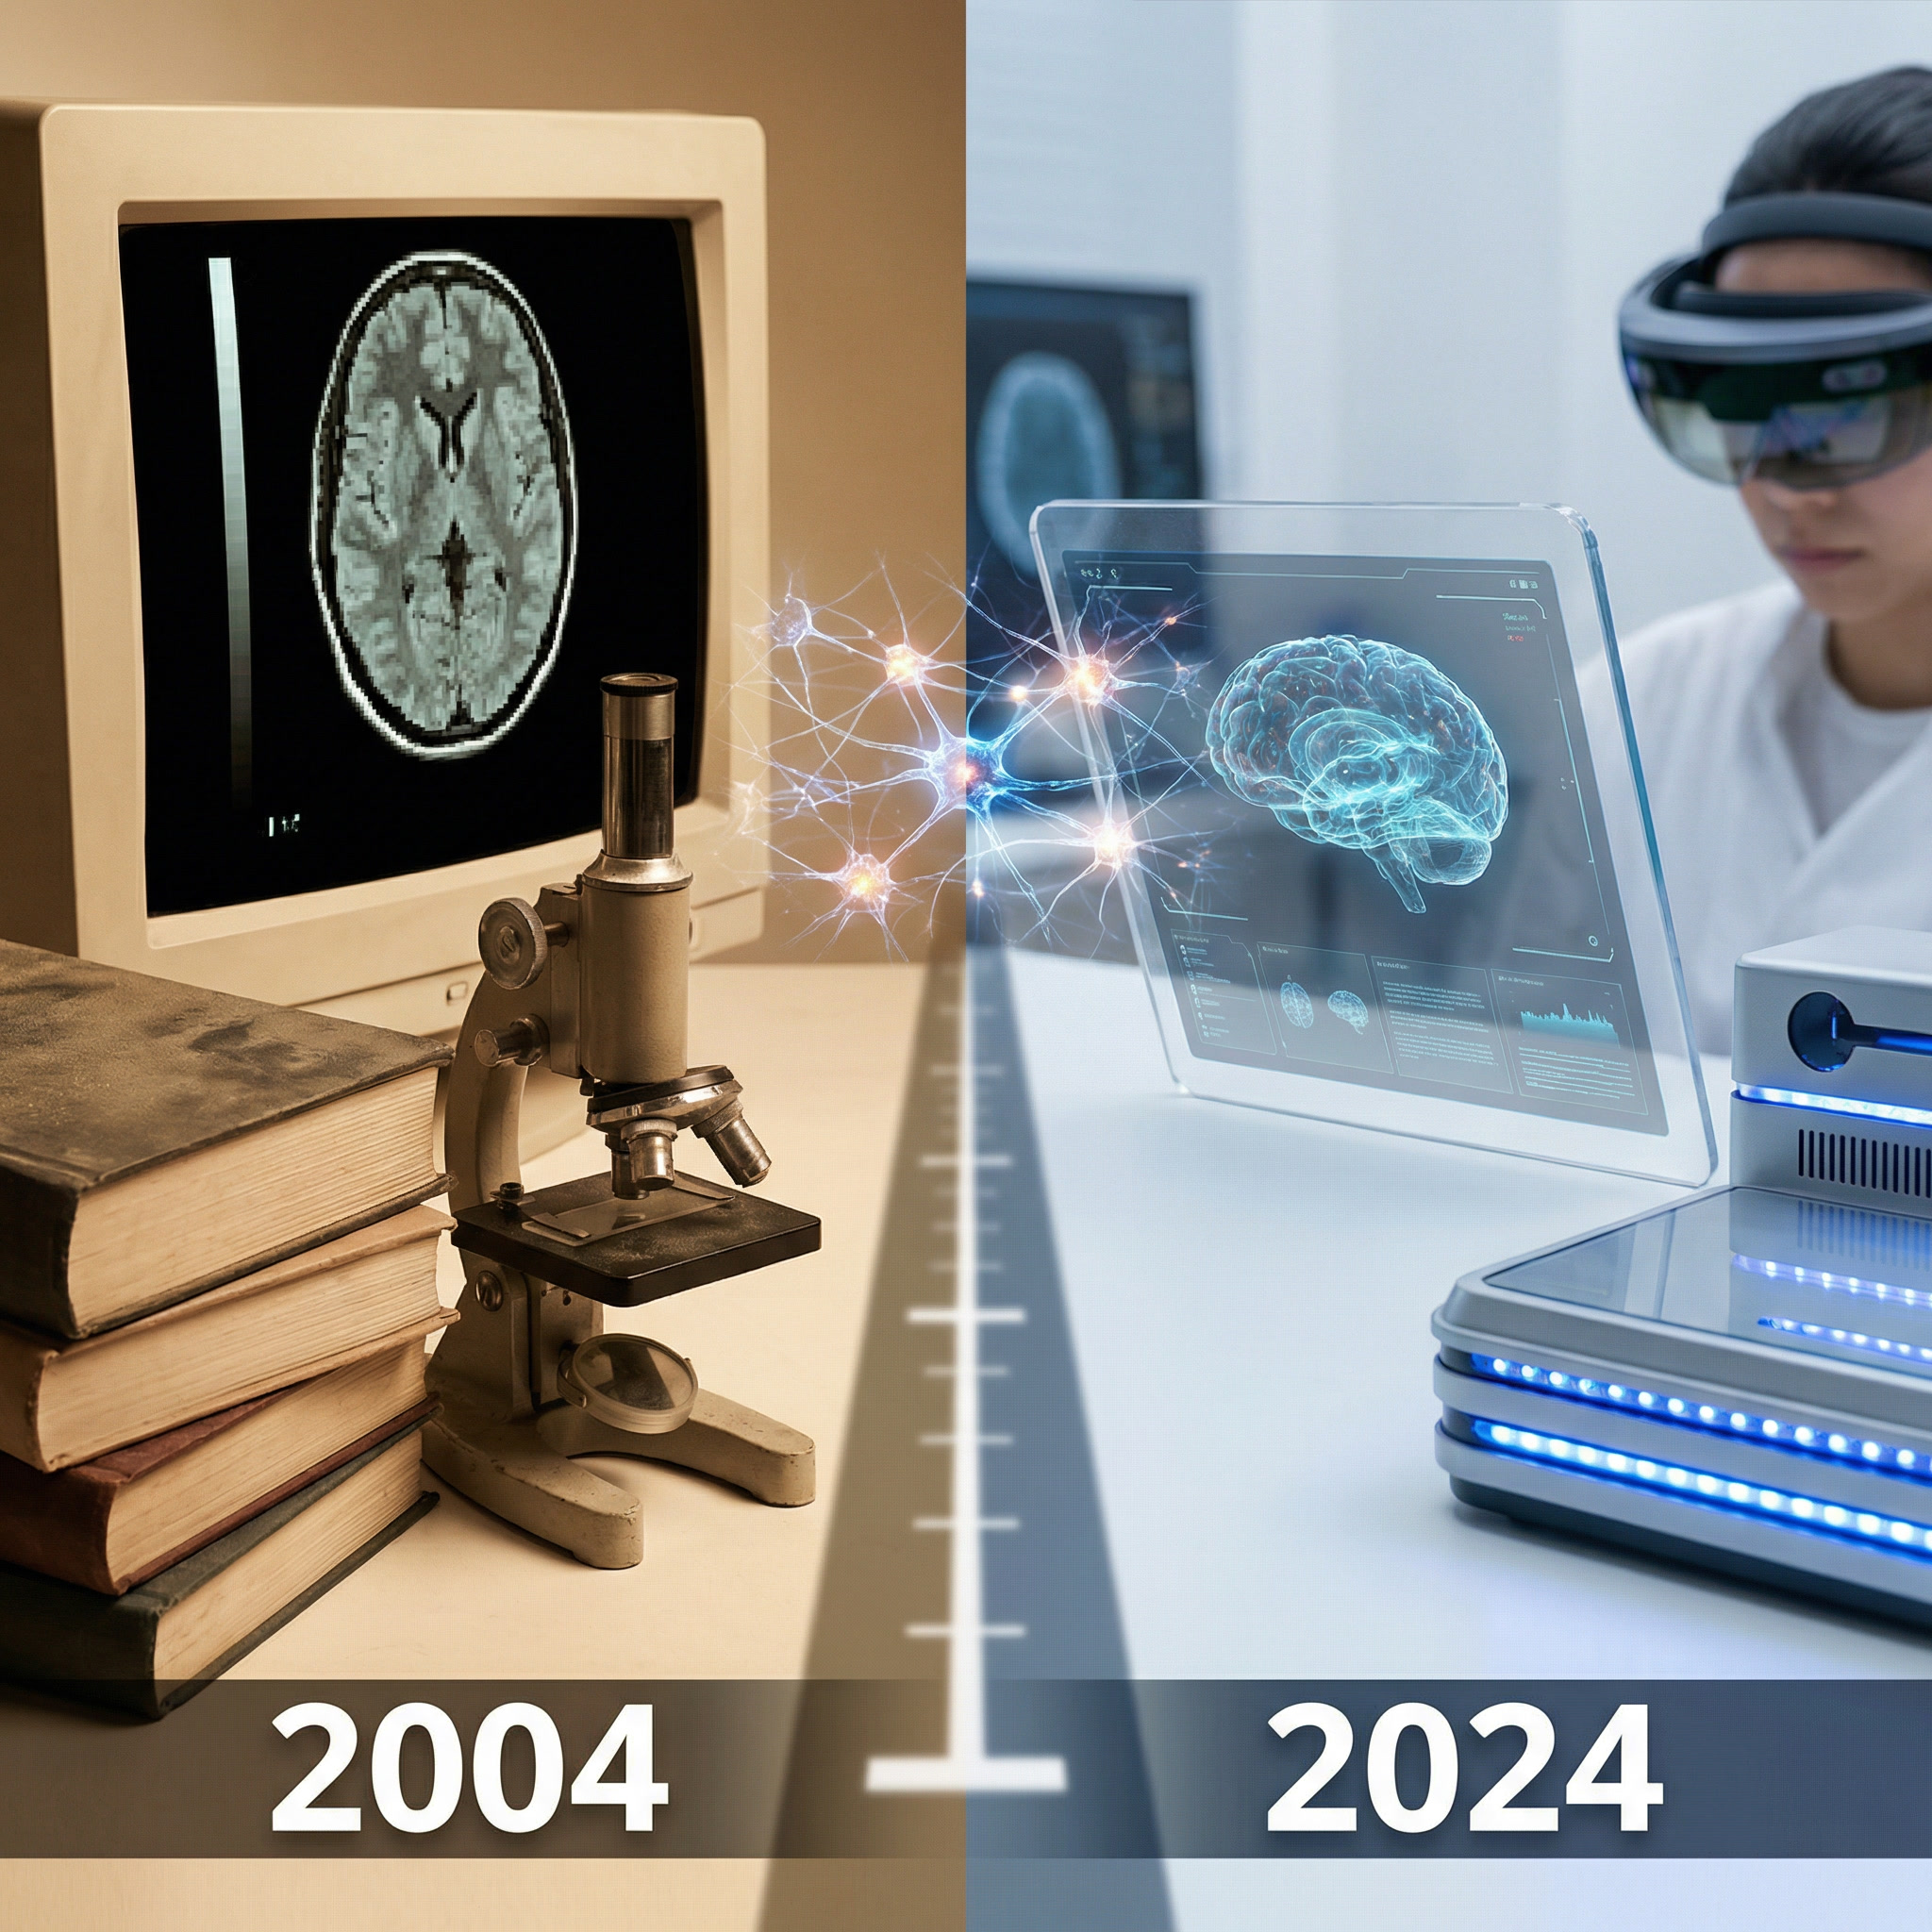

Pijnwetenschap evolueert sneller dan richtlijnen kunnen bijhouden. Het probleem is niet dat de kennis ontbreekt, het probleem is dat ze zelden de spreekkamer bereikt.

Centrale sensitisatie, het onderscheid tussen nociceptieve, neuropathische en nociplastische pijn, de rol van descenderende modulatie: geen academische luxe, maar de mechanismen achter therapierespons, therapiefalen en chronificatie.

Heb je echt een MRI nodig?